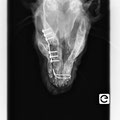

Il les remercie du fond du coeur et peut annoncer une bonne nouvelle : les fils ont été enlevé de sa machoire! Il rejoindra sa nouvelle famille d'accueil mercredi !

Message de Béatrice de Cani Nursing : "Tout va très bien (les fils et les agrafes ont été retirés) et le chirurgien est TRES satisfait !! Bien sûr, il ne faut toujours pas qu’il mâchouille

d’objets durs et il faudrait refaire une radio de contrôle dans un mois. "